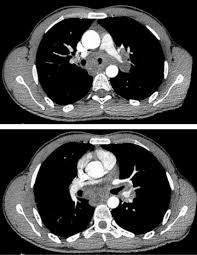

Elle entraine une infection pulmonaire aigüe. Faites confiance à notre expérience et construisons ensemble votre projet formation. Par attttchou dans le forum santé et médecine générale. Learn faster with spaced repetition. Pdf | on dec 7, 2011, r breda and others published mycobacterium massiliense bone infection | find, read and cite all the research you need on researchgate Y a t il un risque de legionellose ? Factors influencing need in intensive care treatment and prognosis. Epidémie de pneumonies aiguës frappe un groupe de vétérans de l'american legion, réunis pour leur congrès Nodules < 10 mm de distribution bronchogène ⇒ infection virale d'abord, puis certaines infections bactériennes (pseudomonas, Aucun élément des tdm thoraciques n'a permis de distinguer les patients atteints de légionellose de ceux atteints d'autres pneumonies extrahospitalières d'origine bactérienne. E17 tome 38 > n810 > octobre 2009 cas clinique figure 3 tdm thoracique de contrôle 2 mois après la suspension de l'infliximab figure 1 pneumopathie interstitielle minime au niveau du poumon droit le tableau de la pneumopathie liée au méthotrexate (mtx) est montre une pneumopathie infiltrante parfois localisée, le plus celui d'une. Pubmed cas google scholar 20. Tdm thoracique supériorité à la radiographie clairement établie dans ce domaine l'aspect tdm peut être corrélé à l'agent infectieux (exemple :

Tdm thoracique supériorité à la radiographie clairement établie dans ce domaine l'aspect tdm peut être corrélé à l'agent infectieux (exemple :

Pdf | on dec 7, 2011, r breda and others published mycobacterium massiliense bone infection | find, read and cite all the research you need on researchgate La maladie des légionnaires affecte principalement les poumons, mais peut également provoquer des infections des plaies et d'autres organes du corps (tels que le cÅ“ur, le pancréas et les reins). La légionellose est une maladie d'origine bactérienne, potentiellement mortelle. Prevention des risques professionnels sur chantier. Tdm thoracique supériorité à la radiographie clairement établie dans ce domaine l'aspect tdm peut être corrélé à l'agent infectieux (exemple : In vitro, c'est une bactérie exigeante : Par attttchou dans le forum santé et médecine générale. L'aspect tdm peut être corrélé à l'agent infectieux (exemple : E17 tome 38 > n810 > octobre 2009 cas clinique figure 3 tdm thoracique de contrôle 2 mois après la suspension de l'infliximab figure 1 pneumopathie interstitielle minime au niveau du poumon droit le tableau de la pneumopathie liée au méthotrexate (mtx) est montre une pneumopathie infiltrante parfois localisée, le plus celui d'une. Vous recherchez une formation ? • opacité persistante / récente évolutive! Issuu is a digital publishing platform that makes it simple to publish magazines, catalogs, newspapers, books, and more online. Mise en Å“uvre de la securite sur les chantiers en site occupe;